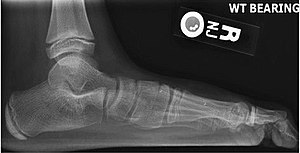

Для диагностики плоскостопия используют данные рентгенографии с рентгенометрией и плантографии при отпечатке подошвы стопы. По выраженности проявлений выделяют три степени продольного и четыре степени поперечного плоскостопия; продольное плоскостопие может сочетаться с любой степенью поперечного плоскостопия. Предварительный диагноз «плоскостопие» может быть выставлен ортопедом на основании физикального осмотра или анализа изображений, полученных при помощи подоскопа или плантографа. Определяются правильность расположения анатомических ориентиров стопы и голеностопного сустава, объём движений и углы отклонения стопы, реакция сводов и мышц на нагрузку, особенности походки, особенности износа обуви[4][2][3].

Другим методом диагностики продольного плоскостопия является измерение расстояния между бугристостью ладьевидной кости (костный выступ, находящийся ниже и спереди от медиальной лодыжки) и поверхностью опоры. Измерение проводят обычной сантиметровой линейкой в положении осматриваемого лица стоя. У взрослых мужчин это расстояние должно быть не менее четырёх сантиметров, у взрослых женщин не менее трёх сантиметров. Если соответствующие цифры ниже указанных границ, констатируется понижение продольного свода. Диагностика плоскостопия включает также анализ внешнего вида обуви пациента — при продольном плоскостопии происходит снашивание внутреннего края каблука и подошвы. Типичным проявлением симптоматического продольного плоскостопия является боль, зависящая от нагрузки, с возможной локализацией в средней части или во всей стопе. Продольное плоскостопие отрицательно влияет на всю биомеханику нижних конечностей, приводя к перегрузке медиальной группы мышц бедра, стабилизирующих голень, что проявляется энтезопатией «гусиной лапки» и в ряде случаев симптомами, сходными с клиническими проявлениями остеоартроза коленного сустава. Причиной типичных для продольного плоскостопия, но односторонних изменений, чаще всего является разница в длине ног (симптомы возникают на стороне более длинной ноги). Поперечное плоскостопие проявляется характерным внешним видом, а именно исчезновением поперечного свода и некоторыми другими объективными признаками[4][1].